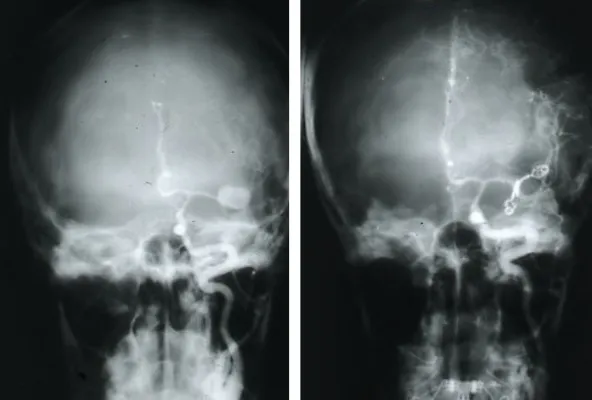

El objetivo terapéutico fundamental es el cierre precoz del aneurisma para prevenir el resangrado. Existen dos modalidades principales de tratamiento:

- Embolización endovascular: se introduce un catéter a través de una arteria periférica hasta llegar al aneurisma, donde se depositan espirales (coils) u otros materiales que rellenan el saco aneurismático y lo excluyen de la circulación.

- Cirugía (clipaje): mediante una intervención neuroquirúrgica se coloca un clip metálico en el cuello del aneurisma para cerrarlo definitivamente e impedir que la sangre entre en su interior.

Además del cierre del aneurisma, es necesario tratar las complicaciones asociadas a la hemorragia subaracnoidea, como el vasoespasmo (contracción de las arterias cerebrales que puede producir isquemia secundaria) y la posible hidrocefalia, que puede requerir la colocación de un drenaje ventricular.